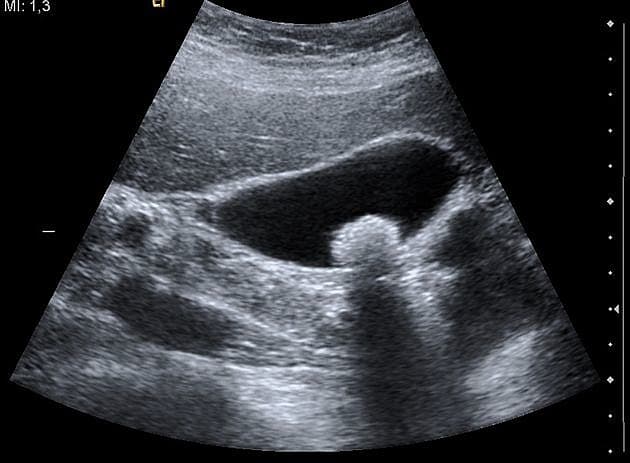

Galdeblæresten er hyppigt forekommende, oftest asymptomatiske og giver kun sjældent årsag til komplikationer. Rasmussen et al. beskriver, at der mangler evidens for, om den kliniske strategi skal være kolecystektomi eller ”watchful waiting” hos patienter med ukompliceret galdestensygdom.